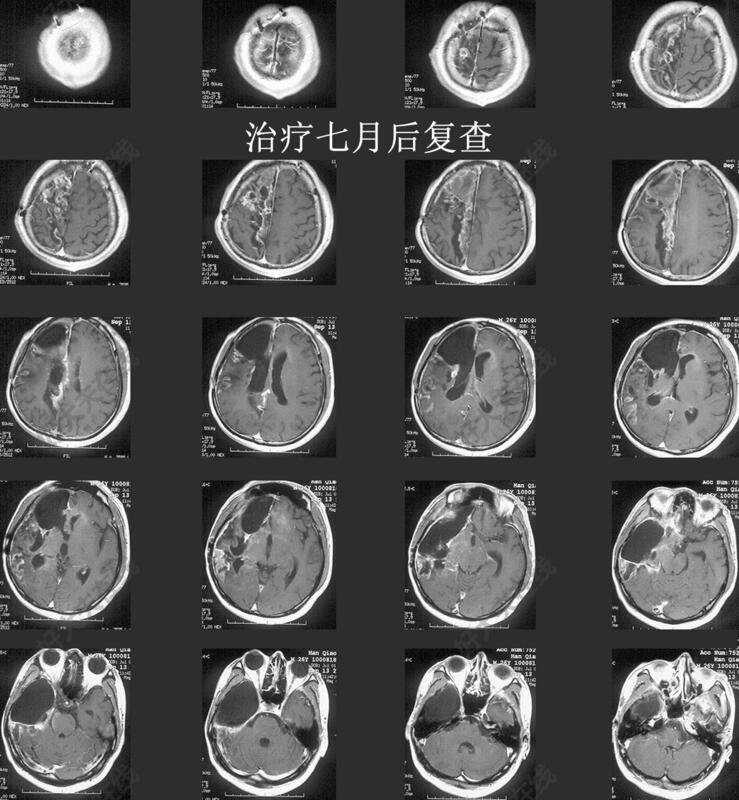

我科入院后,予以加强肠内外营养(鼻饲+静脉输营养液),脱水降压,对症处理。考虑患者一般情况差,口服替莫唑胺都难以耐受,且MGMT未甲基化,予以单药贝伐单抗治疗4周期(3周每周期)。身体指标及抽血指标逐渐恢复,调整为替尼泊苷+贝伐单抗治疗。脑脊液肿瘤细胞阳性,鞘注给甲氨蝶呤,骨髓抑制严重,改为塞替派,耐受较好。继续加强营养,增加康复锻炼,患者体重增加到60kg,增加安罗替尼继续治疗。目前治疗7月,复查脑MRI提示整体稳定,局部一些病灶显著缩小。

- 治疗后7月

一般情况较好,可独立下地行走,体重增加至60kg+。